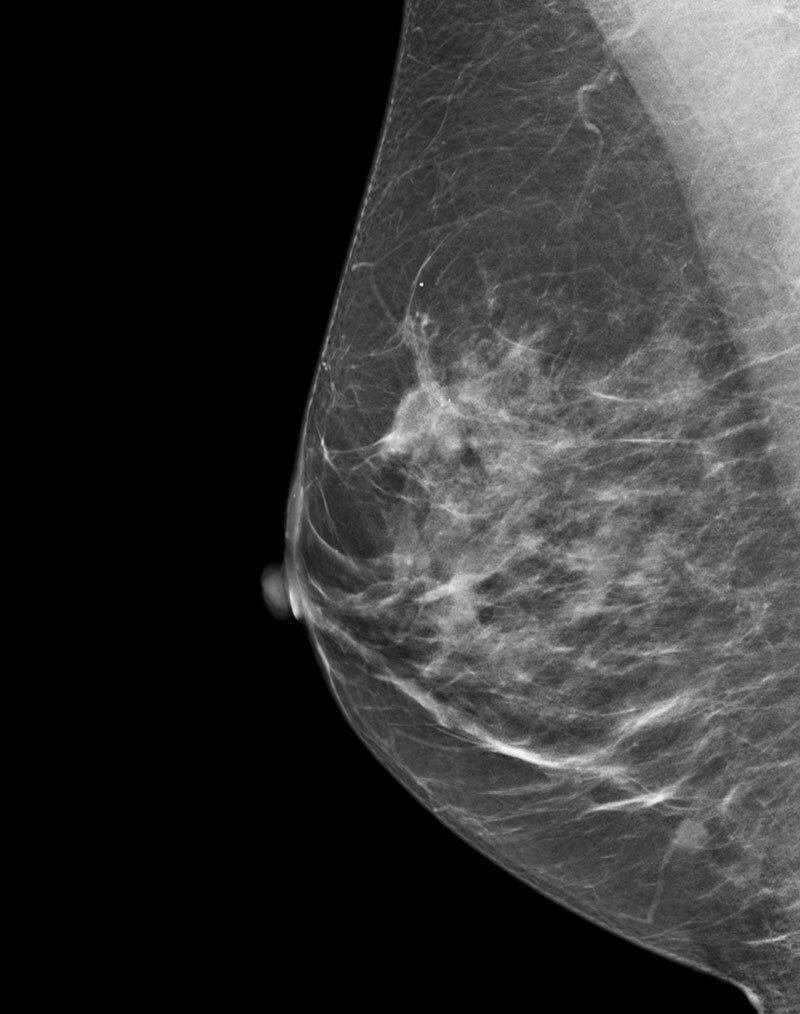

Deep learning in 3D breast image reconstruction

Pristina Recon DL

Pristina Recon DL* pushes 3D mammography past limits, delivering images with greater purity. A paradigm shift born from GE HealthCare’s pioneering AIR™ Recon DL, it operates a dual DL technology that reveals fine details, minimizing artifacts and perceived noise1,2